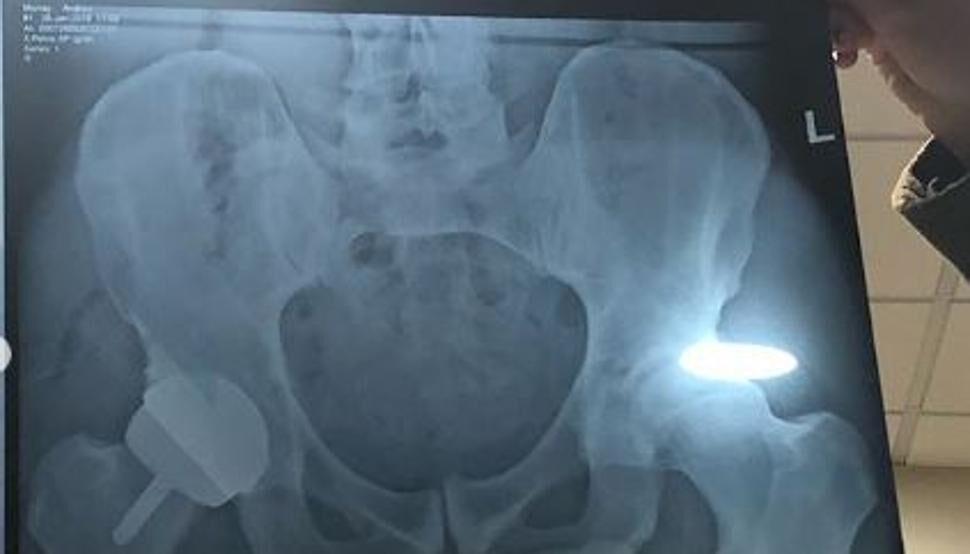

De momento, en pleno postoperatorio, Murray ya ha esbozado una sonrisa tras la locura que ha generado en las redes sociales una radiografía del escocés. Andy cometió un descuido y dejó al descubierto, además de su cadera, una íntima parte de su cuerpo. El pene del escocés se hizo viral en pocos minutos.

"Con suerte, este será el final de mi dolor en la cadera. Ahora tengo una cadera de metal", escribía acompañando la fotografía. Era el mensaje que subía Andy, acompañando la fotografía de la radiografía a su cuenta de Instagram.

Sus fans no pararon por alto el descuido y comenzaron a comentar los atributos del tenista.